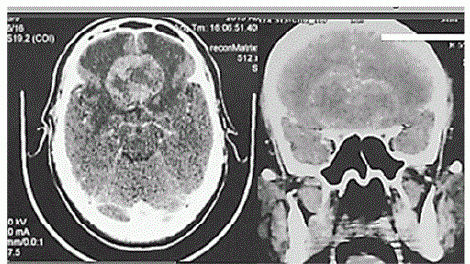

Acervo pessoal.

Considere um paciente de 59 anos de idade, com 90 kg, hipertenso e tabagista. Ele é levado ao hospital por familiares em razão de cefaleia persistente e progressiva. Os familiares relatam, ainda, alteração de comportamento há aproximadamente dois meses, associada à diminuição global de força. Ao exame, o paciente está pouco colaborativo, irritado, com fala inapropriada e hiposmia, sem deficits focais ao exame. Constatam-se AC = RC2T com BNF; FC = 82 bpm; AP = MVF sem RA; FR = 18 irpm; PA = 150 mmHg x 85 mmHg; e SatO2 = 97%. É realizada a tomografia computadorizada (TC) de crânio, conforme a imagem apresentada.

Com base nesse caso clínico e nos conhecimentos médicos correlatos, julgue os itens a seguir.

Lesões com o volume semelhante ao da lesão do caso clínico tendem a evoluir com maior morbimortalidade e dificuldade cirúrgica de ressecção completa.

A tomografia evidencia importante edema citotóxico adjacente à lesão, motivo pelo qual se deve iniciar com altas doses de corticoide.